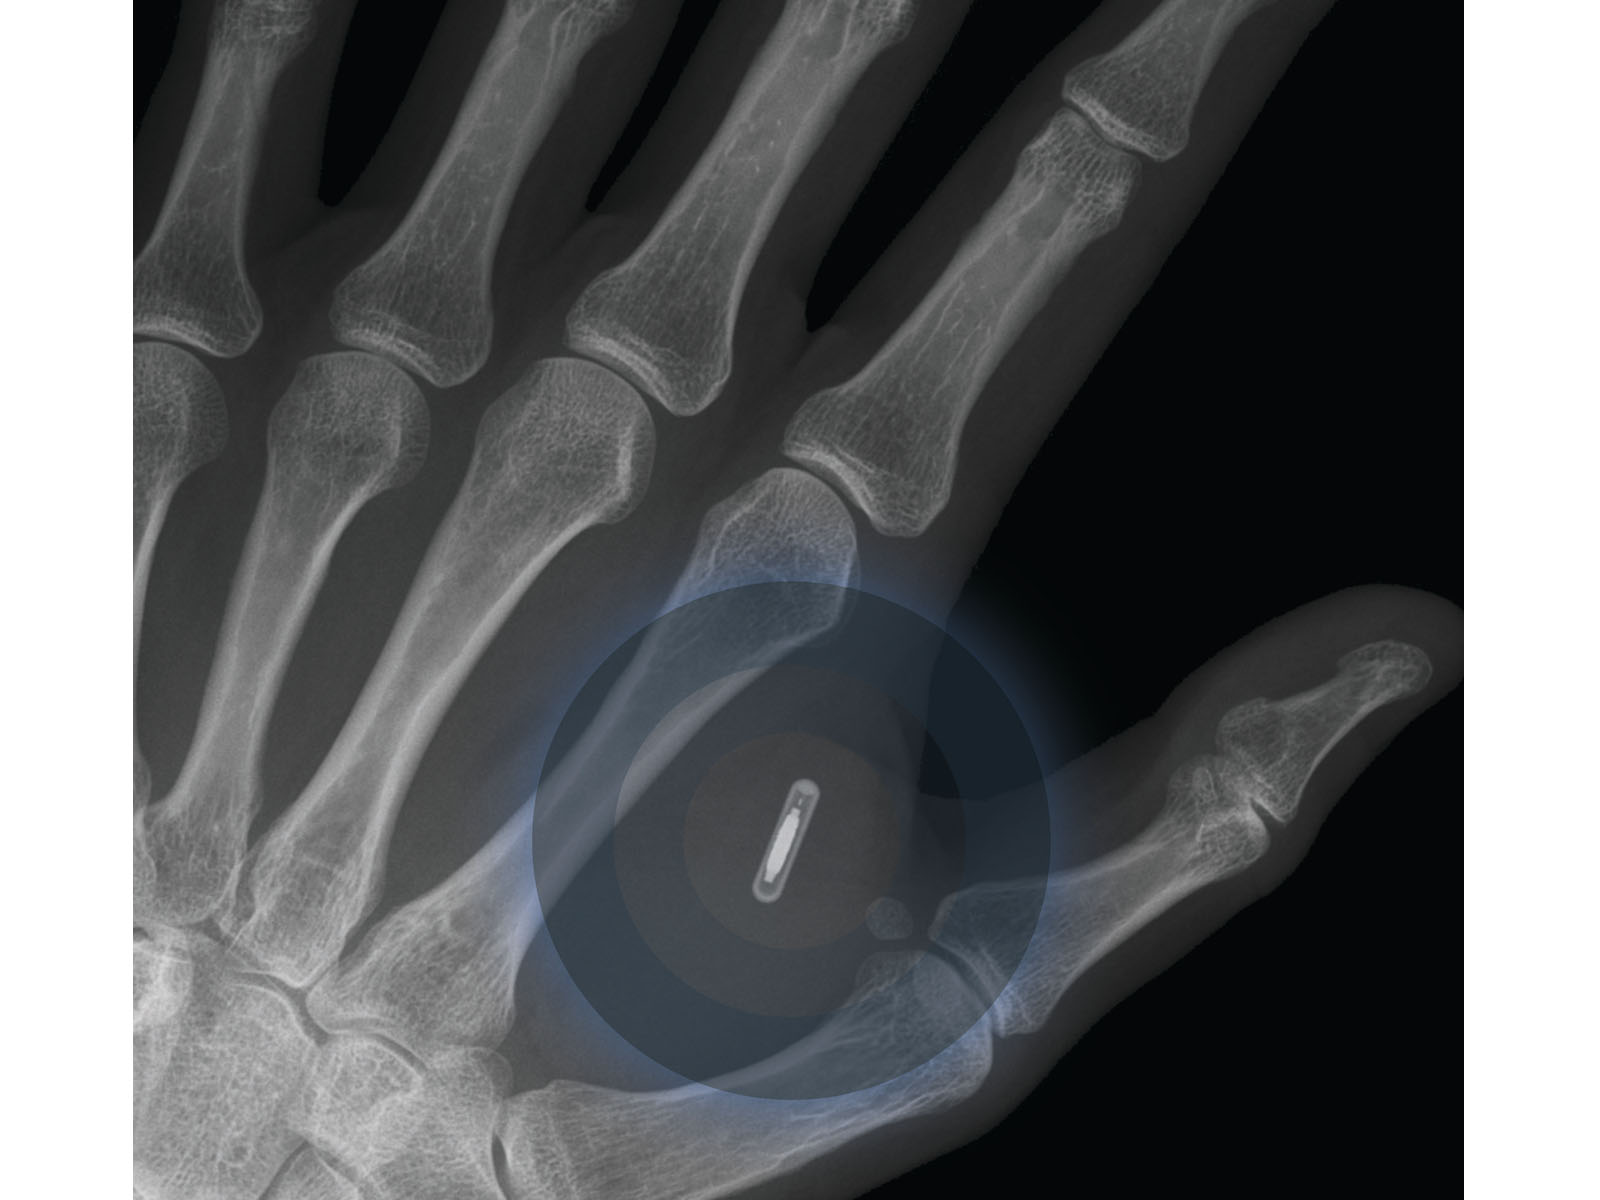

Ein winzig kleiner Mini-Chip implantiert zwischen Daumen und Zeigefinger macht es möglich. Nicht größer als ein Reiskorn. Statt Pin-Codes und Passwörter reicht eine einfache Bewegung mit der Hand, individuell per App "programmiert". Bio-Hacking nennt sich dieser neue Trend, der immer mehr Anhänger in allen Bevölkerungsschichten findet.